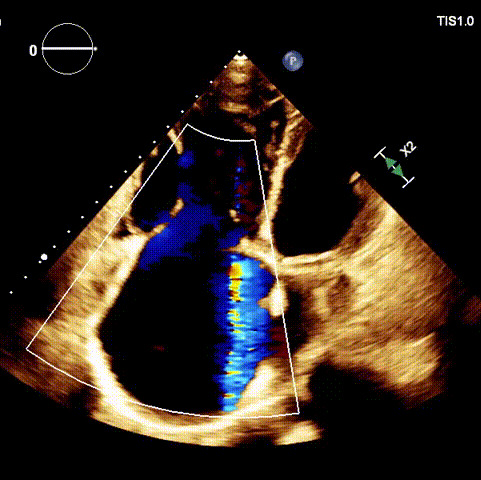

術后超聲

近日,廈門大學心血管病醫(yī)院王焱教授帶領的結構性心臟病團隊,成功應用LuX-Valve Plus經血管三尖瓣置換系統(tǒng),為一例高危三尖瓣重度反流患者開展經血管三尖瓣置換手術。此次手術系LuX-Valve Plus人工瓣膜在福建省的首例植入,手術過程順利,術后患者三尖瓣反流顯著改善,標志著由葛均波院士團隊作為主要研究者的LuX-Valve Plus經血管三尖瓣置換系統(tǒng)全國多中心臨床研究的再一次成功實踐,為三尖瓣介入治療的醫(yī)學循證打下了夯實的基礎。  、